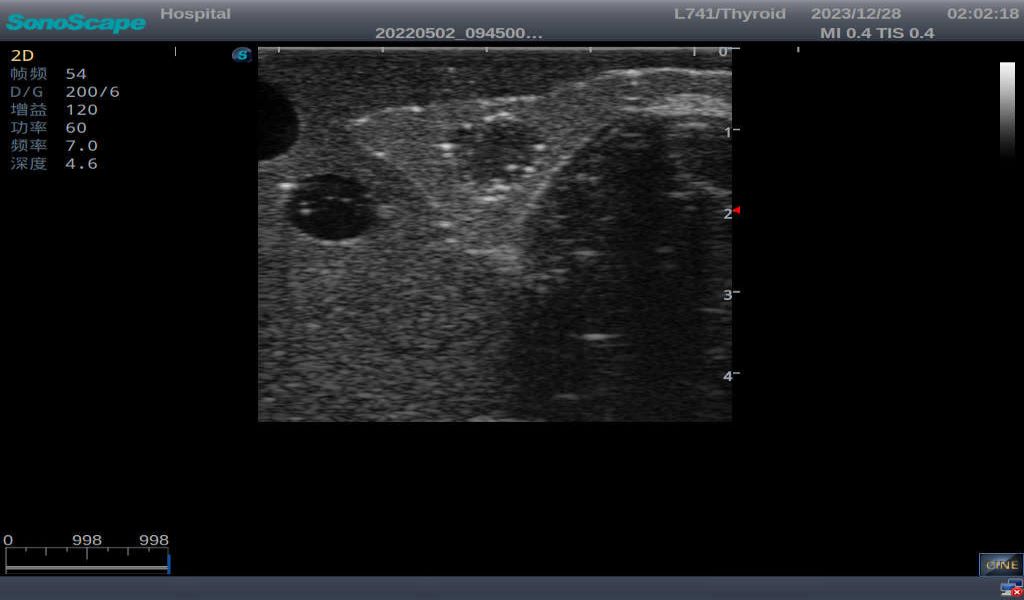

Thyroid adenoma with well-defined border and smooth uniform halo